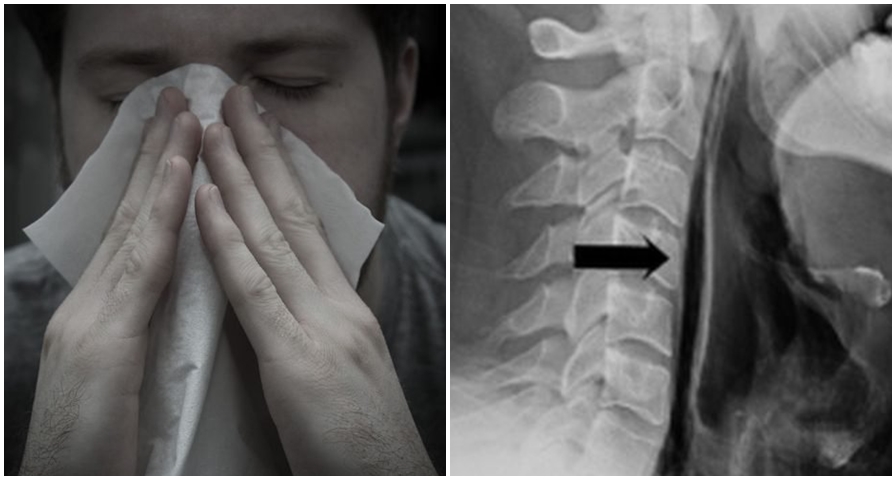

Sering tahan bersin, tenggorokan pria ini akhirnya pecah